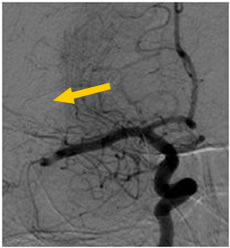

当院で行われた血栓除去術の実際の症例をお示しします。1例目は65歳男性、自宅にて動けなくなっているところを発見されました。軽度意識障害、重度の左片麻痺にて当院に救急搬送、NIHSS17点、心房細動を認めました。頭部MRI(図4)にて右大脳半球に矢印のように虚血巣の出現あり、MRA(図5)にて矢印のように右中大脳動脈の描出なく、緊急にて血管撮影を施行しました。バルーン付きのガイディングカテーテルを入れて、血栓より遠位にマイクロカテーテルを入れて、血栓の遠位からステント(Trevo provue 4×20mm)を展開後、血栓を回収しました。その後の撮影では閉塞していた血管はTICI2bまで再開通しており、治療直後から患者さんの左片麻痺は改善を認め、翌日のMRIでも梗塞巣は広範とならず、治療17日後に自宅退院しました。現在は社会復帰しており、元のお仕事にも戻っております。(図6、7、8、9参照)

図6:総頚動脈撮影の正面では青矢印の様に、右中大脳動脈が閉塞しています |